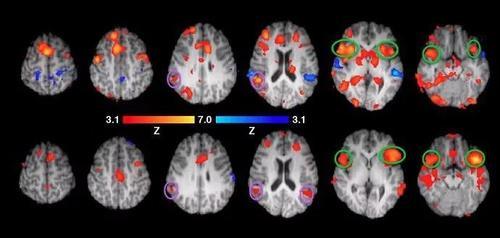

一个多世纪后,要反驳这个谬论也非常简单,因为脑科学的研究与技术已经发展到可以直接看到这个人在思考、记忆、说话、听音乐时大脑的工作情形了。

大脑扫描图像